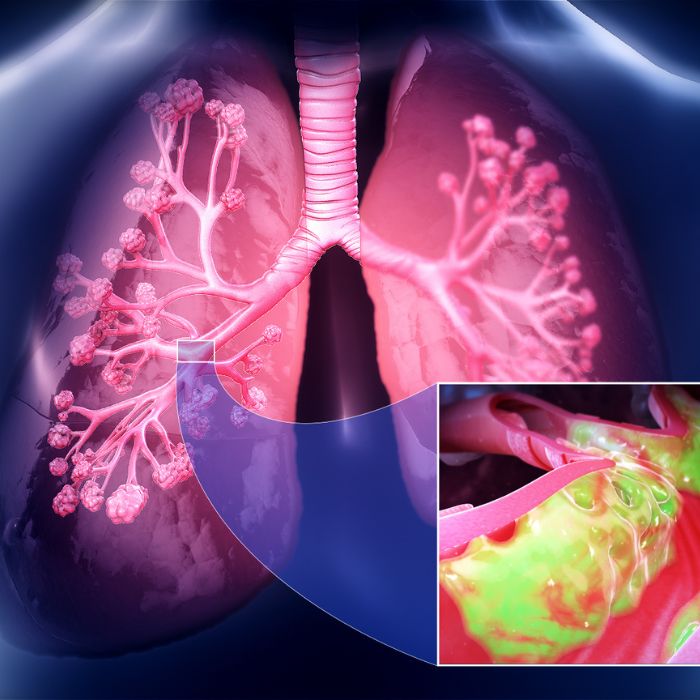

Chest Diseases

Asthma, COPD, pneumonia, tuberculosis, bronchitis, lung cancer, pleurisy, cystic fibrosis, emphysema, pneumothorax, COVID-19, pulmonary edema

Asthma Treatment

Our asthma care offers personalized plans to control and manage your condition effectively, allowing you to lead an active life.

Chronic Lung Disease

Portable oxygen concentrator provides supplemental oxygen, enhancing mobility and improving quality of life for easier breathing every day.